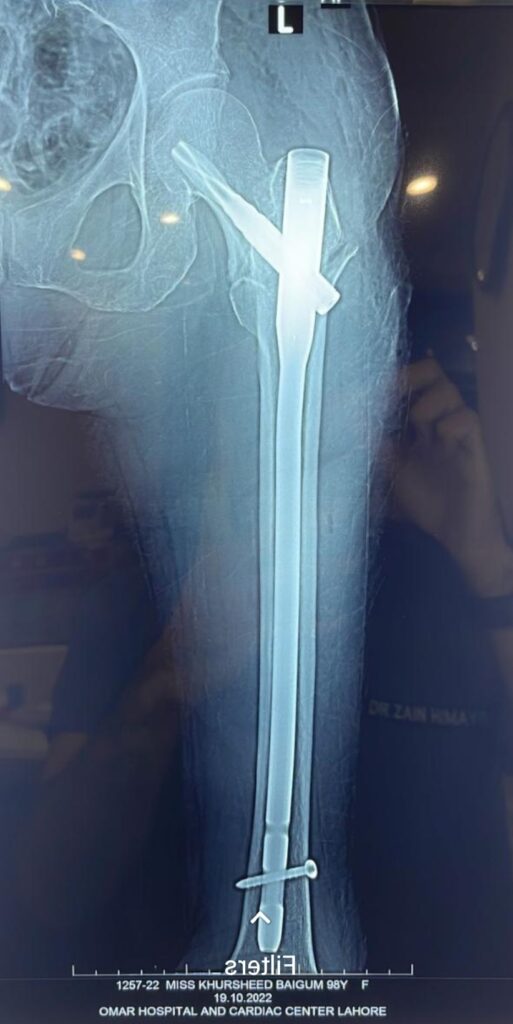

Partial Hip Replacement (Hemiarthroplasty)

The Orthopedic Doctor replaces only the femoral head, which leaves the natural socket intact.